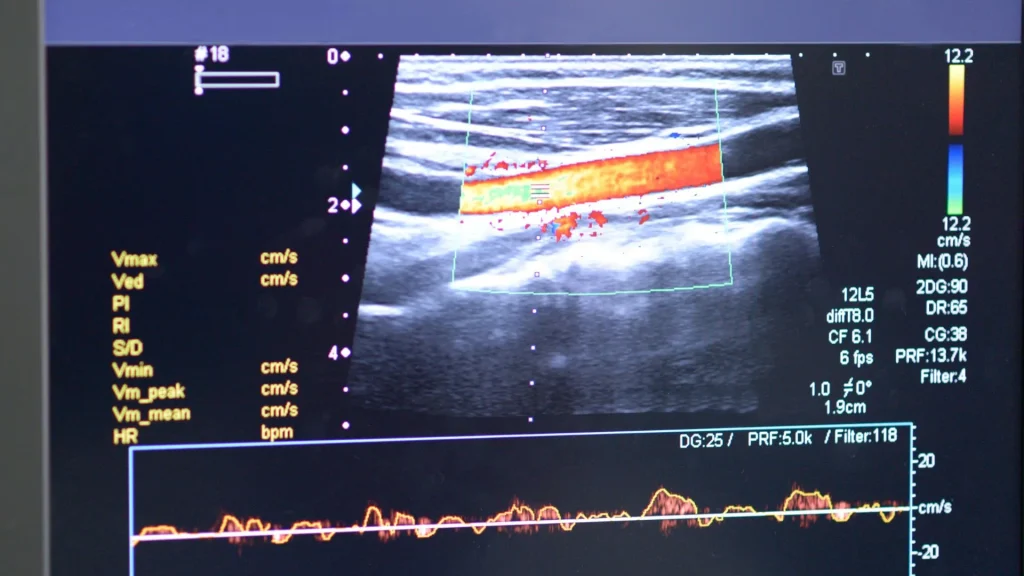

Melalui USG portable, mahasiswa dapat langsung melihat struktur organ tubuh manusia secara real time. Hal ini membantu mereka memahami hubungan antara teori anatomi dan kondisi nyata pasien dengan lebih baik, menjadikan pembelajaran lebih kontekstual dan mendalam.

Dengan paparan rutin terhadap citra ultrasound, mahasiswa menjadi lebih peka terhadap variasi anatomi dan tanda-tanda patologi. Ini meningkatkan ketelitian mereka dalam membuat interpretasi diagnostik sejak dini.